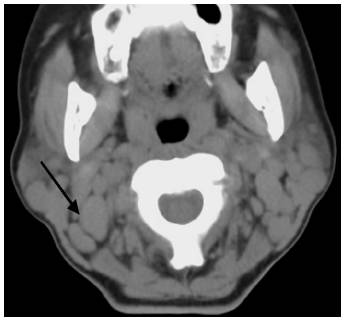

图4 女性,56岁,箭头显示右侧颈部ⅡA区转移性低分化癌。

ⅡB区:双侧颈静脉后方(图5)。